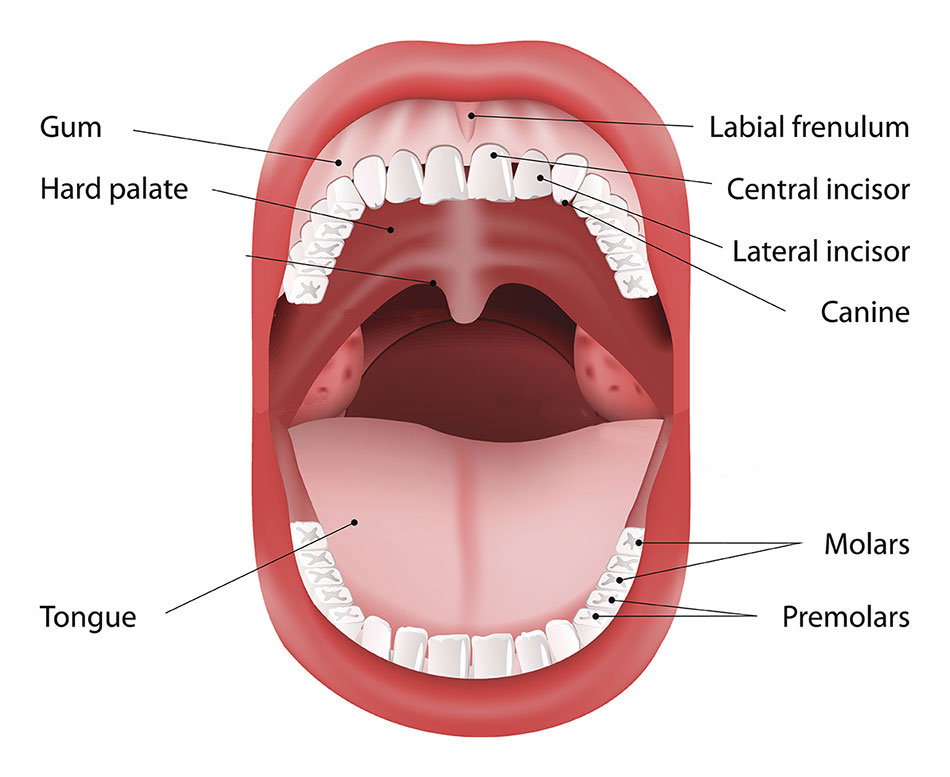

Oral Cancer Mouth Cancer Anatomy Headandneckcancerguide Org

Oral Cancer Wikipedia

Stages Of Oral Cancer Mouth Cancer Headandneckcancerguide Org

Mouth Cancer Or Oral Cancer Types Symptoms Stages